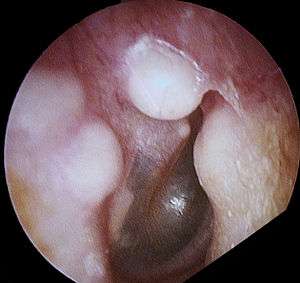

| Osteoma of external auditory meatus | |

An osteoma (plural: "osteomata") is a new piece of bone usually growing on another piece of bone, typically the skull. It is a benign tumor.